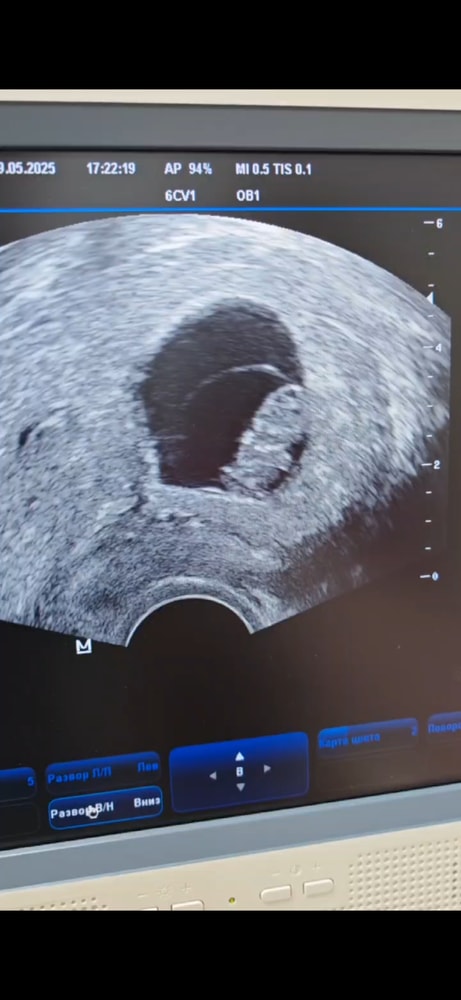

Тоже была на узи в 8 Нед и 3 дн Ктр 21.6 мм ПЯ- 36 мм ЖМ- 5мм ЧСС- 144 Тоже опережает на 3 дня По ктр 8нед и 6 дн Такая же креветуля,с зачатками ручек и ножек🫶🏻 С 9 недель ровно нахожу сб доплером! По линии роста волос,доплер к уху,чтобы точно уловить,бежит как паровоз,ни с чем не спутать🫶🏻 Растите ♥️